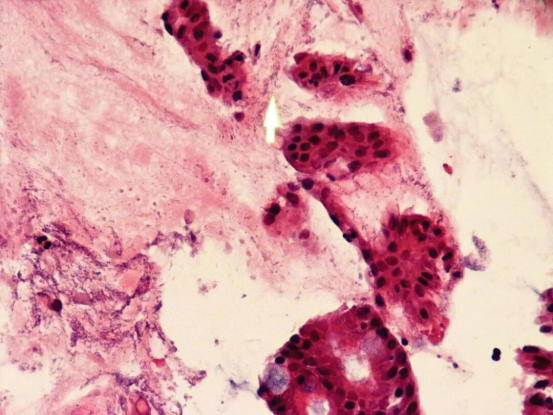

6.HP的斯坦氏染色法:

在全自动特殊染色平台上染色。

图7_胃体小弯组织HP的斯坦氏染色,HP呈杆状、黑色。细胞核黑色,对照背景黄色(40X)

从染色结果和方法学上对比来看,HP的HE染色较难观察,只有在HP大量繁殖的情况下才能确诊。IHC染色,相较与HE染色,易于观察判断,但是其染色时间较长且成本较高。W-S染色效果较好,但银染过程繁琐,且苯二酚不稳定、不易保存,要临时配制,配制试剂所需的玻璃器皿也必需非常清洁,否则就会造成染色的失败,而且染色时间较长,需要在56℃温箱染色1h以上。全自动特殊染色配合斯坦氏特殊染色液检测胃镜标本HP更标准和简便,且易于判读、染色质量稳定。